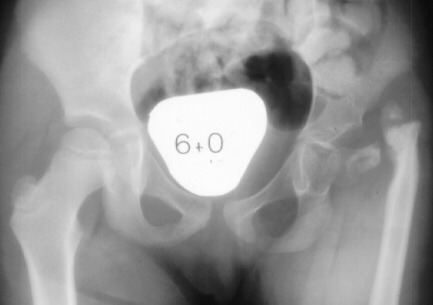

The

correct diagnosis for this pattern of deformity is proximal femoral

focal deficiency (PFFD).

This

is a common combination of deformities.

insult that causes these deformities occurs between weeks 10 and

12 after conception.

There

is no known specific cause of these deformities.